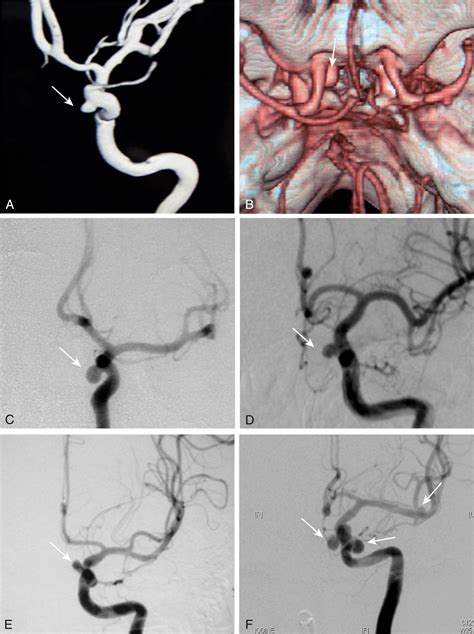

• Surgical Clipping: A neurosurgeon places a small metal clip across the neck of the aneurysm to stop blood flow into it.

• Endovascular Coiling: A minimally invasive procedure where a catheter is threaded through an artery to the aneurysm, and tiny platinum coils are inserted to block off blood flow.